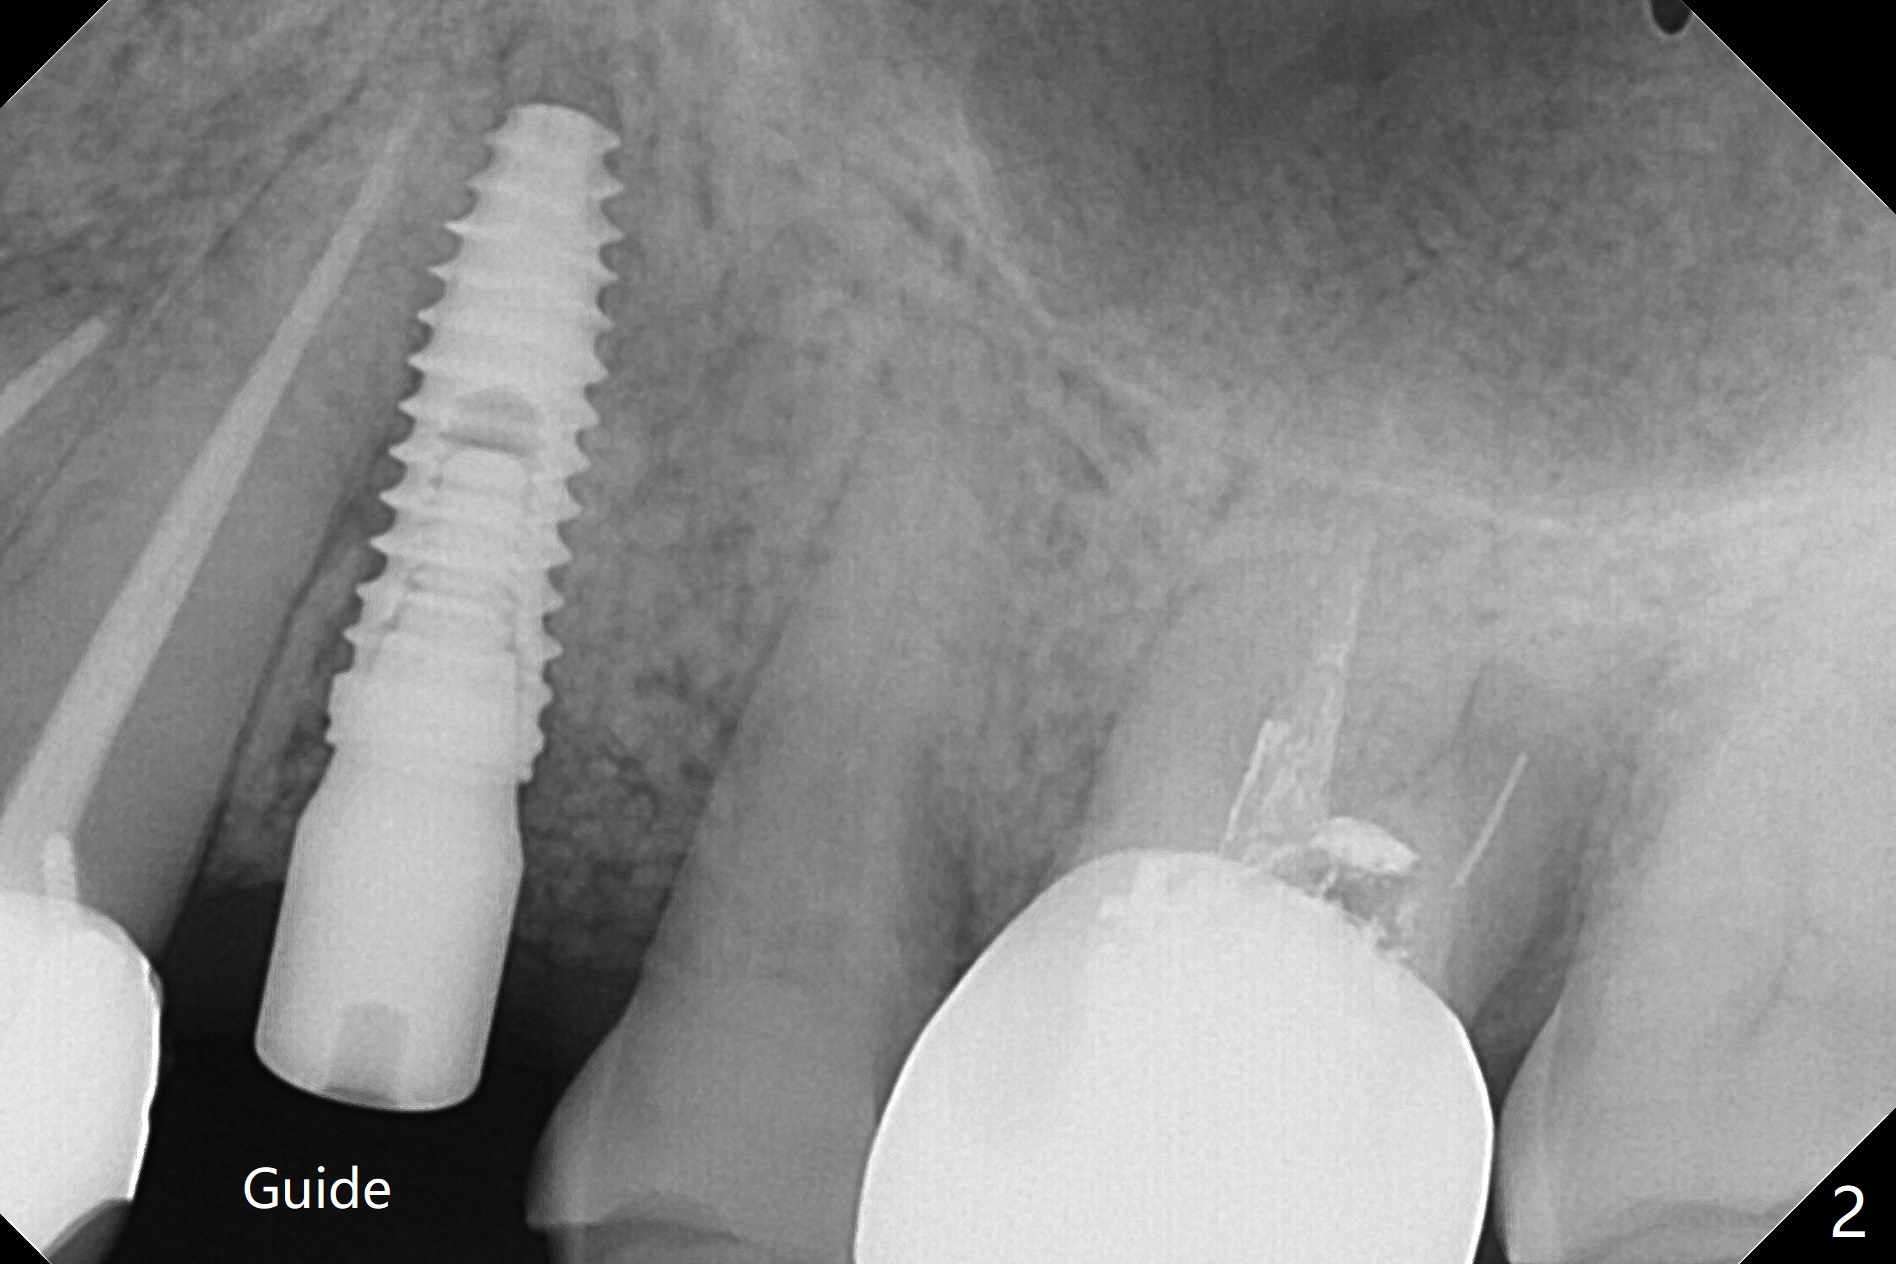

植骨后6个月牙槽窝愈合正常,角化龈和牙槽嵴都宽(图一),导板种植好像不需要切口。利用导板植入,但是离尖牙牙根很近(图二,三)。取出植体后,准备切开改变钻洞方向(图四,五),结果效果不错(图六,七),腭侧骨壁低,安置愈合基台,植骨(图八:*),覆盖胎盘膜,缝合。